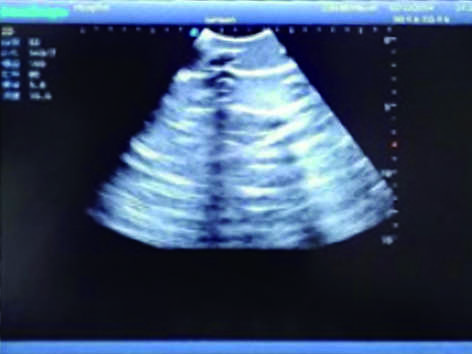

Pneumothorax & Thoracic Closed Drainage Ultrasound Training Model

It is a model covering up from the neck to the umbilicus with body surface markers such as ribs, intercostal space, left and right intercostal arches, armpits and nipples.

3)  Showing clear and real images of the tissues and organs (including muscle and connective tissue, air-containing lung tissue, pleural structure)